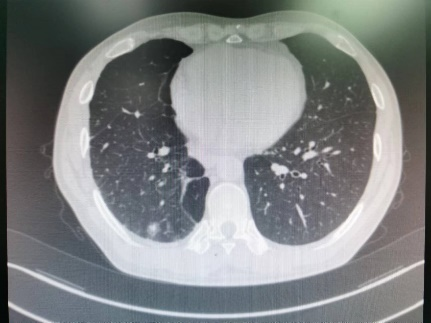

51岁的辛先生和74岁的汪女士均为我院胸外科的肺癌术后随访6年的老患者,辛先生在上月体检时行胸部CT检查发现自己的右侧肺部竟再次长出一个直径约1.5cm的混合磨玻璃结节,而汪女士在近1年来出现右侧胸腹壁疼痛症状,复查胸部CT及骨扫描发现肋骨及胸椎癌转移。出现新发结节令辛先生寝食难安,查出骨转移更是令汪女士惶恐失措。为寻求治疗,两位患者再次来到我院胸外科李少民教授处就诊。

经过周密术前准备后,由胸外科李少民教授、马跃峰副主任医师、马震川主治医师,在放疗CT定位室、超声科的严密配合下为两位患者分别实施了CT引导下、超声引导下的肿瘤冷冻消融术。经过反复地定位及精准地穿刺,团队顺利将冷冻消融针置入肺结节中,经过重复2个循环的“冷冻-复温”,肿瘤经冷冻消融后变成了“冰块”。手术历时约半个小时,患者反应良好,没有明显疼痛及胸闷气短。

“冷冻消融”是近年来兴起的一项新的肿瘤微创治疗技术,相较于微波消融、射频消融等热消融而言更为温和,局部毁损范围更为精确局限,患者痛感大大减弱,因而在晚期转移性肿瘤、复发肿瘤治疗中具有无可替代的优势,在早期良恶性未定的肺小结节治疗中也有重要治疗价值。西安交通大学第二附属医院胸外科已成功开展超声引导下肺肿瘤冷冻消融、CT引导下肺肿瘤冷冻消融、胸壁肿瘤冷冻消融等多种冷冻消融技术。此外胸外科团队还常规开展了肺肿瘤的微波消融、射频消融等多项微创消融技术,积累了丰富的经验。